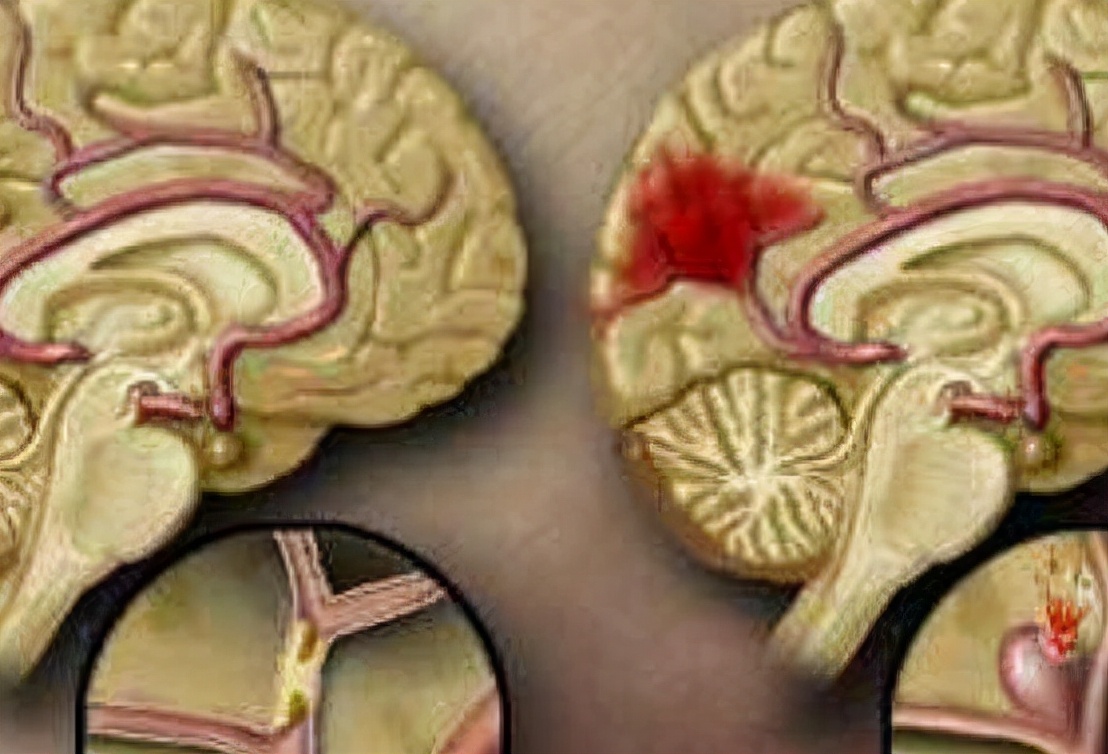

脑出血是指原发性非外伤性的脑实质出血。绝大部分的患者发病部位发生于大脑半球,极小部分的患者发生于脑干和小脑。 生活中脑出血的发病原因复杂,多半主要跟脑血管的病变有关。

另外,脑出血属于神经性疾病,由于长期在高血压的作用下会造成血管破坏,从而引起出血。 脑出血发生时,病人会迅速地出现肢体不协调,言语不清,意识昏迷的临床表现 。

作为早期诊断脑出血的唯一治疗手段,它的准确性非常高。检查颅脑时, 颅内出现高密度影像时,就可以判断此人患上脑出血; 极少数个别情况的患者由于脑出血的面积很小,不易被察觉。